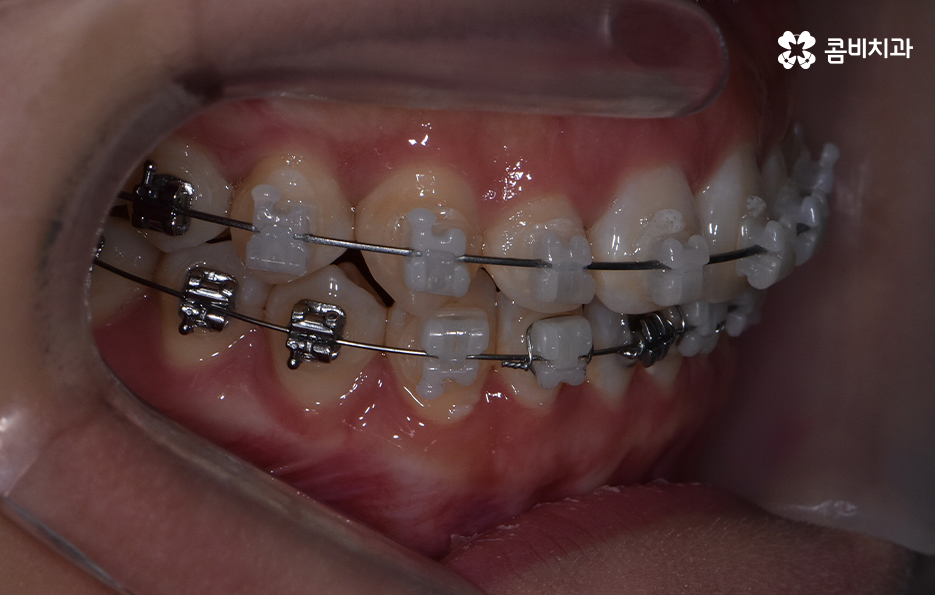

교정 치료는 크게 발치와 비발치치아교정으로 나뉠 수 있는데 비발치치아교정의 경우에는 아무래도 치아가 움직이는 양도 적고 그에 따라 교정 기간도 짧은 편에 해당되고 있어요.

교정을 하게 되면 아무래도 치아와 잇몸이 함께 움직이기 때문에 어느정도는 잇몸이 약해질 가능성이 있는데 비발치치아교정의 경우에는 치아의 이동이 큰 편은 아니기 때문에 발치교정에 비해서는 잇몸이 약해지는 정도 및 확률이 줄어들 수 있어요

반면에 발치교정의 경우에는 최소 1년 6개월 ~ 2년 이상의 교정 기간이 소요되며 치아가 빠진 공간에 나머지 치아들이 메우면서 치아의 이동이 비발치치아교정에 비해 많기 때문에 그에 따라 치아는 물론 치조골의 이동도 감안해야 하므로 치료 기간도 더 오래 걸리고 잇몸도 좀더 약해질 수 있는 확률이 발치교정에 비해서는 높은 편으로 볼 수 있는데요.